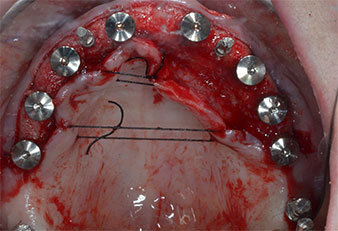

A causa dell'osso relativamente duro (D2) in quest'area, le sedi dell'impianto di 10 mm nelle posizioni 11 e 21 sono state finalizzate con un trapano rotante da 4 mm di diametro, in combinazione con un contrangolo chirurgico W&H WS-75 L, il motore per impianto W&H Implantmed e il modulo opzionale Osstell ISQ di W&H. Al contrario, a causa dell'osso morbido, le sedi posteriori sono state preparate a un diametro finale di 3 mm utilizzando lo strumento Piezomed I3P. Gli impianti sono stati infine posti per via transgengivale sull'osteointegrato per tre mesi (Figg. 6-10). La protesi dentaria esistente è stata mantenuta su quattro impianti provvisori (Fig. 8).